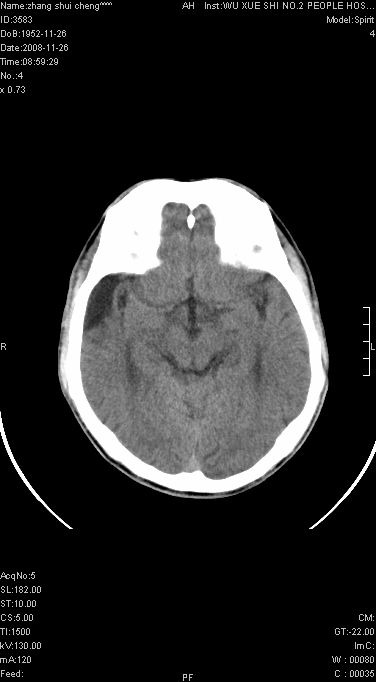

标题: CT16800:男.68.肢体无力多年请会诊 [打印本页]

男.68.肢体无力多年

请问是蛛网膜囊肿.还是软化灶.原有中风

支持右侧颞区蛛网膜囊肿。

蛛网膜囊肿,软化灶周围脑沟应该受牵拉,扩大

颞部膨胀,多考虑蛛网膜囊肿